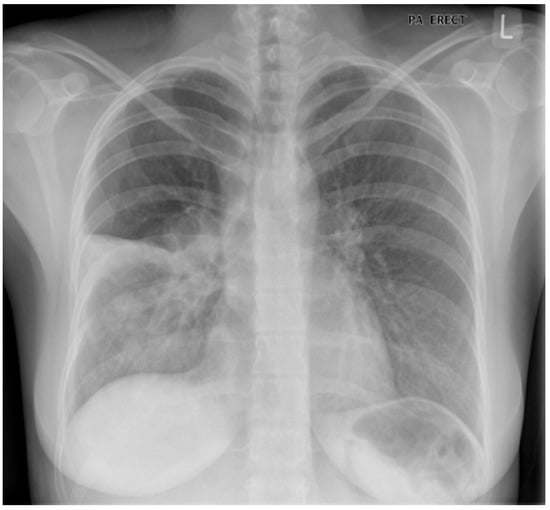

A 67 year old woman with known chronic obstructive pulmonary disease (COPD) presents with a three-day history of increased breathlessness and a cough productive of sputum; the sputum is darker in colour than usual, and greater in volume. Her chest X-ray is illustrated below as Figure 1. The X-ray suggests consolidation in the right lower lobe. Should this be considered a pneumonia, or an exacerbation of COPD? To start to answer this question, let us first consider the definitions of these two events.

Figure 1.

Right lower lobe consolidation in a patient with known chronic obstructive pulmonary disease (COPD): pneumonia or exacerbation?